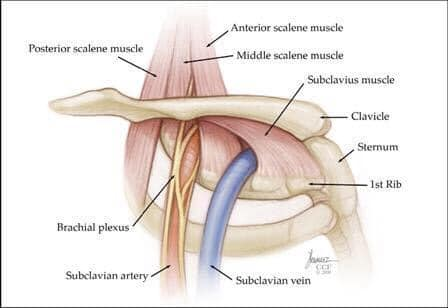

Hội chứng lối thoát ngực là một tình trạng, theo đó triệu chứng được tạo ra từ việc chèn ép các dây thần kinh, mạch máu, hoặc cả hai, vì một lối đi hẹp thông qua một khu vực (lối thoát ngực) giữa nền cổ và nách. Lối thoát ngực được bao quanh bởi cơ, xương và các mô khác. Bất kỳ tình trạng nào gây phì đại hay chuyển động của các mô hoặc gần lối thoát ngực đều có thể gây ra hội chứng lối thoát ngực. Các nguyên nhân thường gặp của hội chứng lối thoát ngực bao gồm chấn thương vật lý như một tai nạn xe hơi, tổn thương lặp đi lặp lại do công việc hoặc các hoạt động liên quan đến thể thao, một khuyết tật bẩm sinh nào đó (chẳng hạn như có một xương sườn phụ), mang thai, tăng cân, và các khối u ở phía trên của phổi (hiếm). Ngay cả một chấn thương dài trong quá khứ có thể dẫn đến hội chứng lối thoát ngực trong hiện tại. Đôi khi các bác sĩ không thể xác định nguyên nhân của hội chứng lối thoát ngực.

Hội chứng lối thoát ngực do căn nguyên thần kinh: loại này đặc trưng bởi sự chèn ép đám rồi thần kinh cánh tay. Đám rối thần kinh cánh tay là một mạng lưới các dây thần kinh xuất phát từ tuỷ sống, kiểm soát vận động của các cơ và cảm giác ở vai, cánh tay và bàn tay. Trong hầu hết trường hợp của hội chứng lối thoát ngực triệu chứng là về thần kinh.

Hội chứng lối thoát ngực do căn nguyên mạch máu: xảy ra khi một hoặc nhiều động mạch, tĩnh mạch dưới xương đòn bị chèn ép.

Nói chung, nguyên nhân của hội chứng lối thoát ngực là ép của các dây thần kinh và mạch máu trong lối thoát ngực, ngay dưới xương đòn. Nguyên nhân của sự chèn ép bao gồm :

Khiếm khuyết bẩm sinh: một xương sườn phụ nằm phía trên xương sườn đầu tiên hoặc một dải sợi chặt nối xương sống với xương sườn.

*Chụp cộng hưởng từ (MRI): Những hình ảnh này có thể giúp xác định vị trí và nguyên nhân gây ra ép các dây thần kinh của đám rối thần kinh cánh tay hoặc động mạch dưới đòn. Những hình ảnh quét cũng có thể tiết lộ bất kỳ dị tật bẩm sinh – chẳng hạn như một dải sợi kết nối xương sống của bạn với xương sườn hoặc xương sườn phụ có thể là nguyên nhân gây ra các triệu chứng.